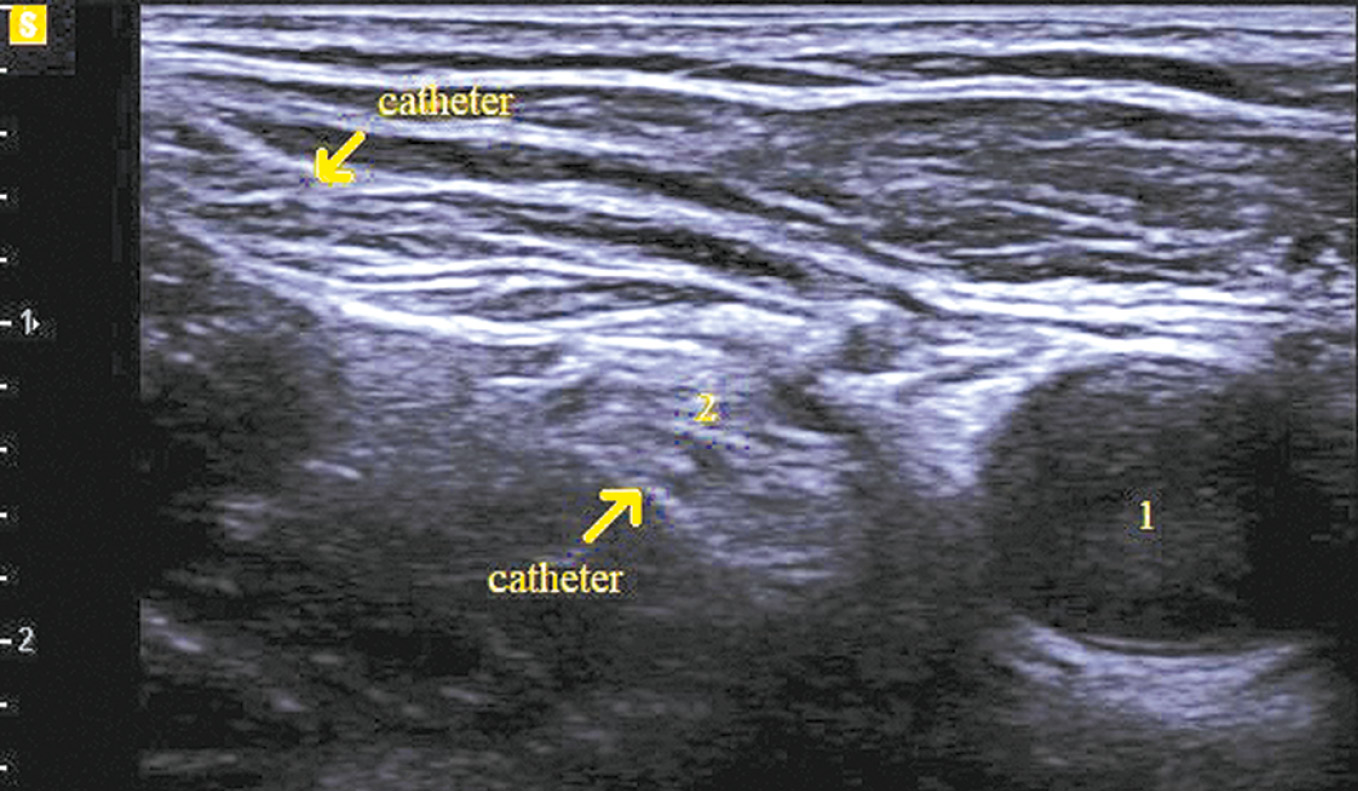

To mitigate the probability of technical complications, regional anesthesia was performed by the same anesthesiologist with expertise in ultrasound-guided regional anesthesia and nerve catheterization. The femoral nerves were catheterized aseptically via the ultrasound-guided technique using a Samsung HM70 Ultrasound System (Samsung Medical, South Korea) and a sterile, disposable Kontiplex Tuohy continuous peripheral nerve block catheter set (B. Braun, Germany). A 15 MHz linear transducer was positioned on the femoral crease to visualize the femoral artery, vein, and nerve (Fig. 1).

Fig. 1. Ultrasound image of the femoral nerve.

Note. 1 — femoral vein, 2 — femoral artery, 3 — femoral nerve.

After the procedure, the catheter was secured with Band-Aid directly to the skin (Fig. 4).

Fig. 4. Fixation of the catheter.